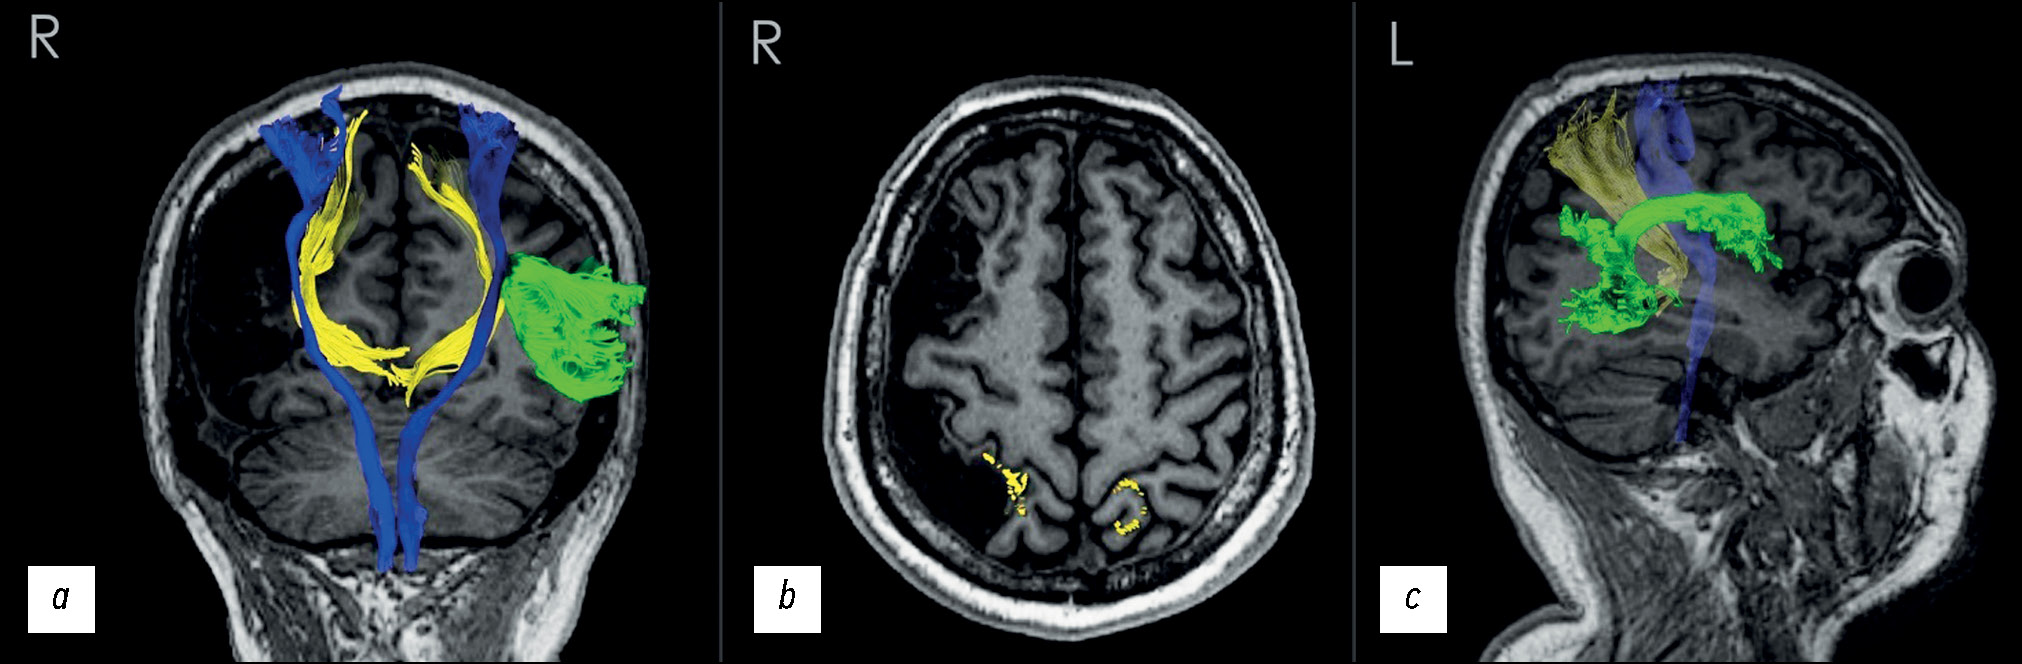

МР-трактография. По результатам МР-трактографии при помощи программного пакета DSI STUDIO в полуавтоматическом режиме удалось выделить пучки кортикоспинальных трактов (рис. 3, синим цветом), дугообразного пучка (рис. 3, салатовым цветом), пути медиальных петель (рис. 3, жёлтым цветом) или DCML (Dorsal column–medial lemniscus pathway — путь заднего столба медиальной петли, далее — путь медиальной петли).

Рис. 3. Реконструированные данные магнитно-резонансной трактографии, наложенные на магнитно-резонансные томограммы, Т1-взвешенные изображения во фронтальной плоскости: а — кортикоспинальные тракты (синий), дугообразный пучок (салатовый), пути медиальных петель (жёлтый); b — проекции пучков пути медиальных петель (жёлтый) в области постцентральных извилин; c — описанные тракты в сагиттальной плоскости (вид со стороны левого полушария с полупрозрачным срезом).

Как видно из рис. 3, все выделенные тракты, кроме дугообразного, оказались симметричны слева и справа. Дугообразный пучок определялся только в левом полушарии. Пучки пути медиальной петли справа проекционно совпадали с оставшейся корой постцентральной извилины, слева — были распределены по передней и задней частям извилин.